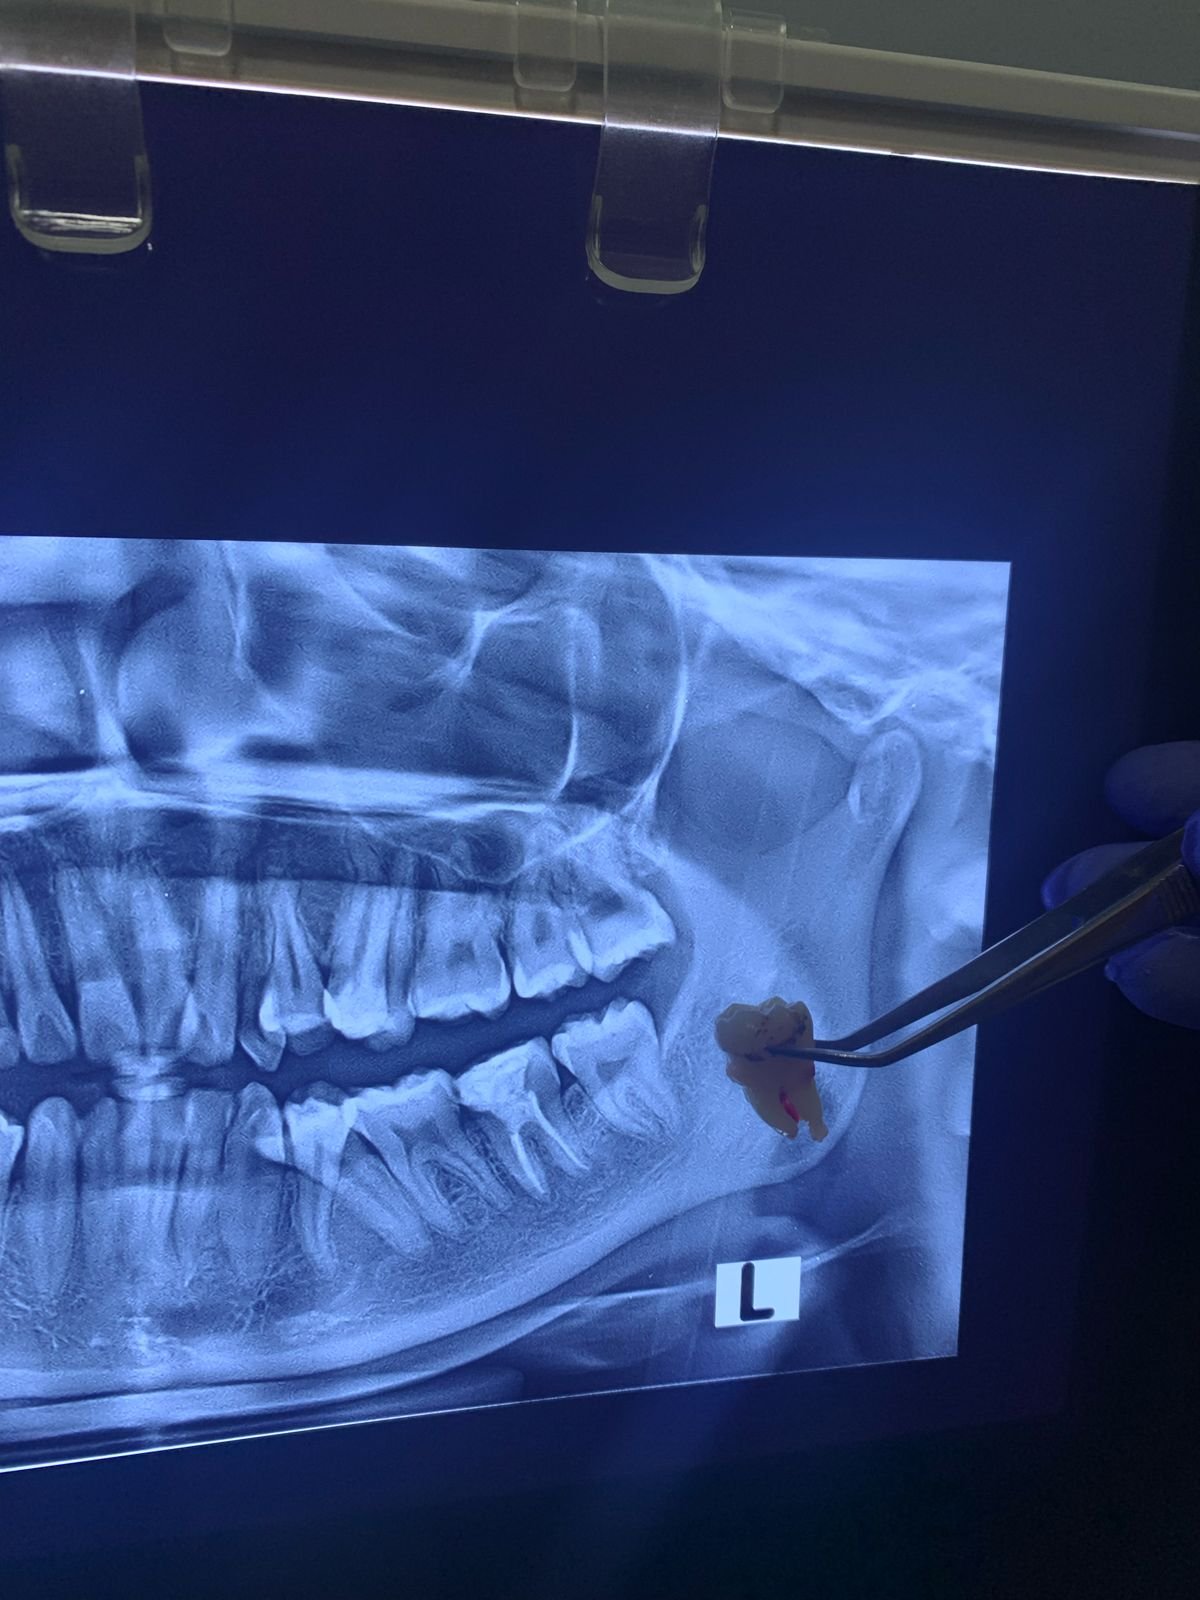

Dokter melakukan rontgen panoramic untuk melihat posisi gigi bungsu dan menilai kondisi pasien.

• Teknologi rontgen panoramic modern.